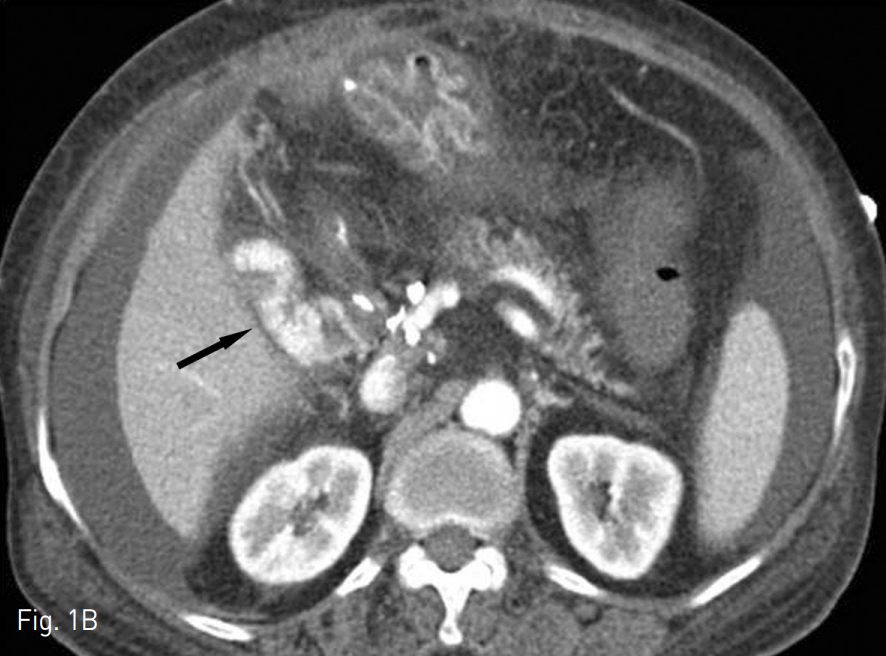

Fig. 1. A 78-year-old female who underwent PPPD 5 years ago presented with hematemesis and hematochezia.

A. CT reveals portal vein thrombosis (arrow) and associated cavernous transformation and ascites.

B. Extravasation of contrast media (arrow) in jejunum suggests active bleeding in afferent loop.